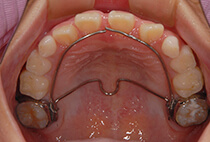

小学2年生の終わり、

「将来は外科矯正が必要」と言われた受け口の女の子。

小学生の成長力を最大限に生かすため、

上顎の成長促進・過蓋咬合の改善・機能訓練を同時にスタートしました。

1年後(小3 → 小4)

かみ合わせもお顔立ちも大きく改善。

その後も機能訓練×かみ合わせの維持をコツコツ継続。

急速拡大装置、上顎前方けん引装置、コルチコトミー

診断の結果は、以下が原因の骨格性反対咬合。

反対咬合でよくあるケースです。

治療方法は、小さな上顎の成長誘導。

急速拡大装置と前方けん引装置を使用します。

成長のピークに合わせて上顎をもう一度拡大し、前歯のかみ合わせをさらに安定化。

成長期の波に合わせることで、より調和の取れた横顔へ。

治療開始から6年後。

治療終了後2年経っても、安定したかみ合わせと自然な横顔をキープ。

2年生で外科矯正と言われた受け口も、4年生になる頃にはすでに「バランスの良いお顔立ち」に。のびのびと成長期を過ごすことができました。